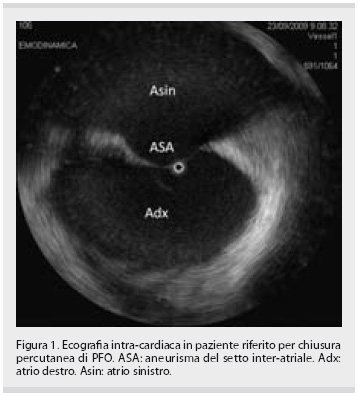

Tips and tricks: come orientarsi tra i vari dispositivi per la chiusura del forame ovale pervio | Giornale Italiano di Cardiologia - Organo ufficiale di Italian Federation of Cardiology e Società Italiana